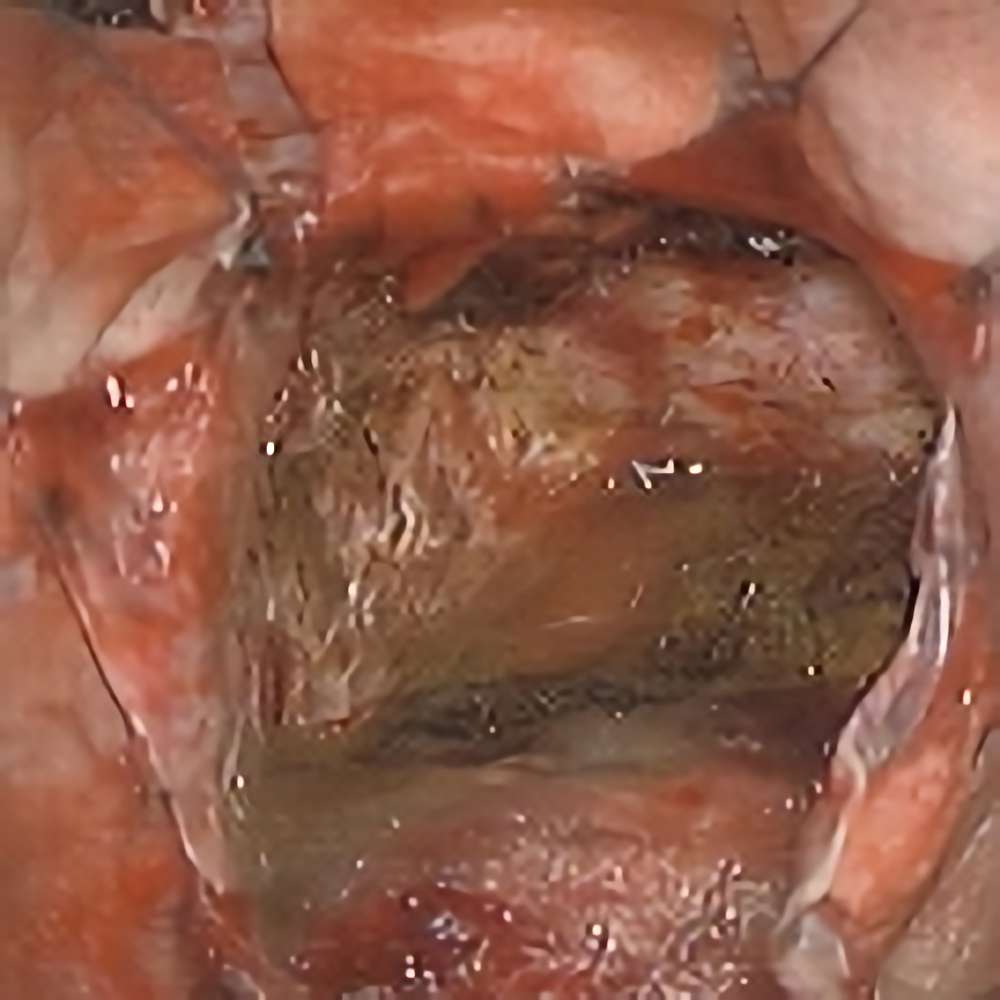

134

'19年10月

70代

左側頭葉膠芽腫

頭蓋内腫瘍摘出術

No.’19_35 摘出 前

No.’19_35  摘出 中

No.’19_35 摘出 後